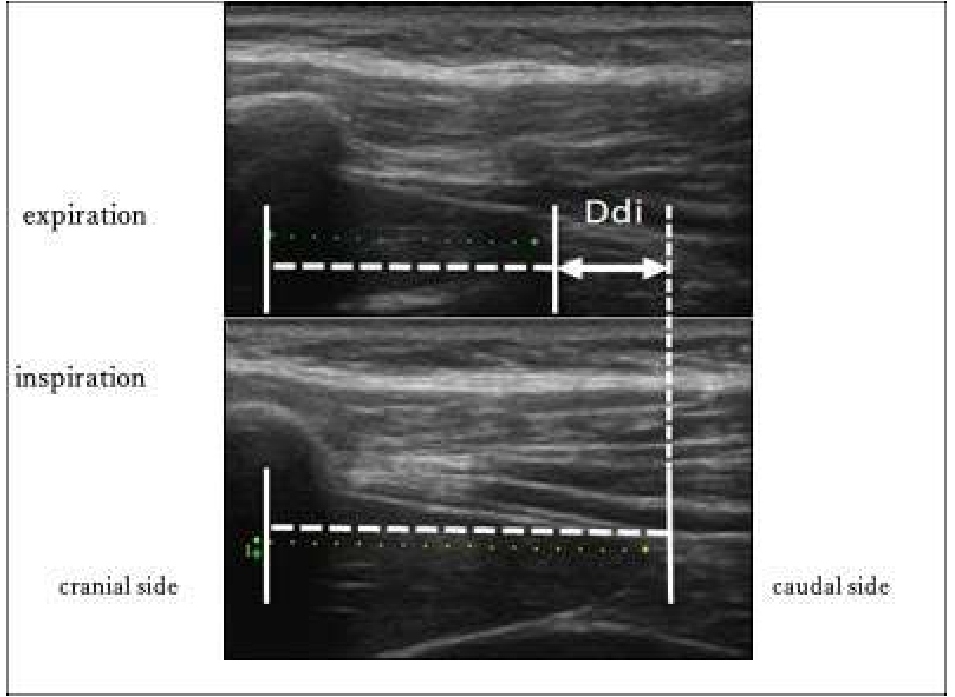

We imaged the distance of diaphragmatic movement (Ddi) and the thickness of the diaphragm (Tdi) using US (7.5 MHz linear probe, Ultrasound System ARIETTA Prologue, B-mode, Hitachi, Japan). The right side of the sites for measuring Ddi and Tdi was set as the region of interest because the left diaphragm is difficult to visualize given the presence of gastrointestinal organs [13-18]. The Ddi was imaged on the right mid-axillary line from the 9th–10th intercostal space to the upper border of the zone of apposition (ZOA) between the midclavicular line and the anterior axillary line. Ddi was defined and measured as the change in the distance from any ribs in the visual field to the diaphragm [14,17,18]. Tdi was imaged at the ZOA on the mid-axillary line. According to the method by Wakai et al.[16], muscle thickness was imaged at the same site, and the difference in the muscle thickness between the end of inspiration and end of expiration was defined as the difference in the Tdi, which was used as an index of the amount of diaphragm activity (Figures 1 and 2).

Figure 1: Distance of diaphragmatic movement (Ddi) in US. Ddi: Distance of diaphragmatic movement; US: Ultrasonography.

In the image analyses [17,18], the following indices of respiratory muscle activity were calculated using the obtained images and an image-analyzing software (Image J®). The ratio of Ddi to height (Ddi/Ht) was also calculated using the following formula: Ddi/Ht (%) = Ddi (cm)/height (cm) × 100. The maximal muscle thickness was measured as Tdi during QB and FAB.